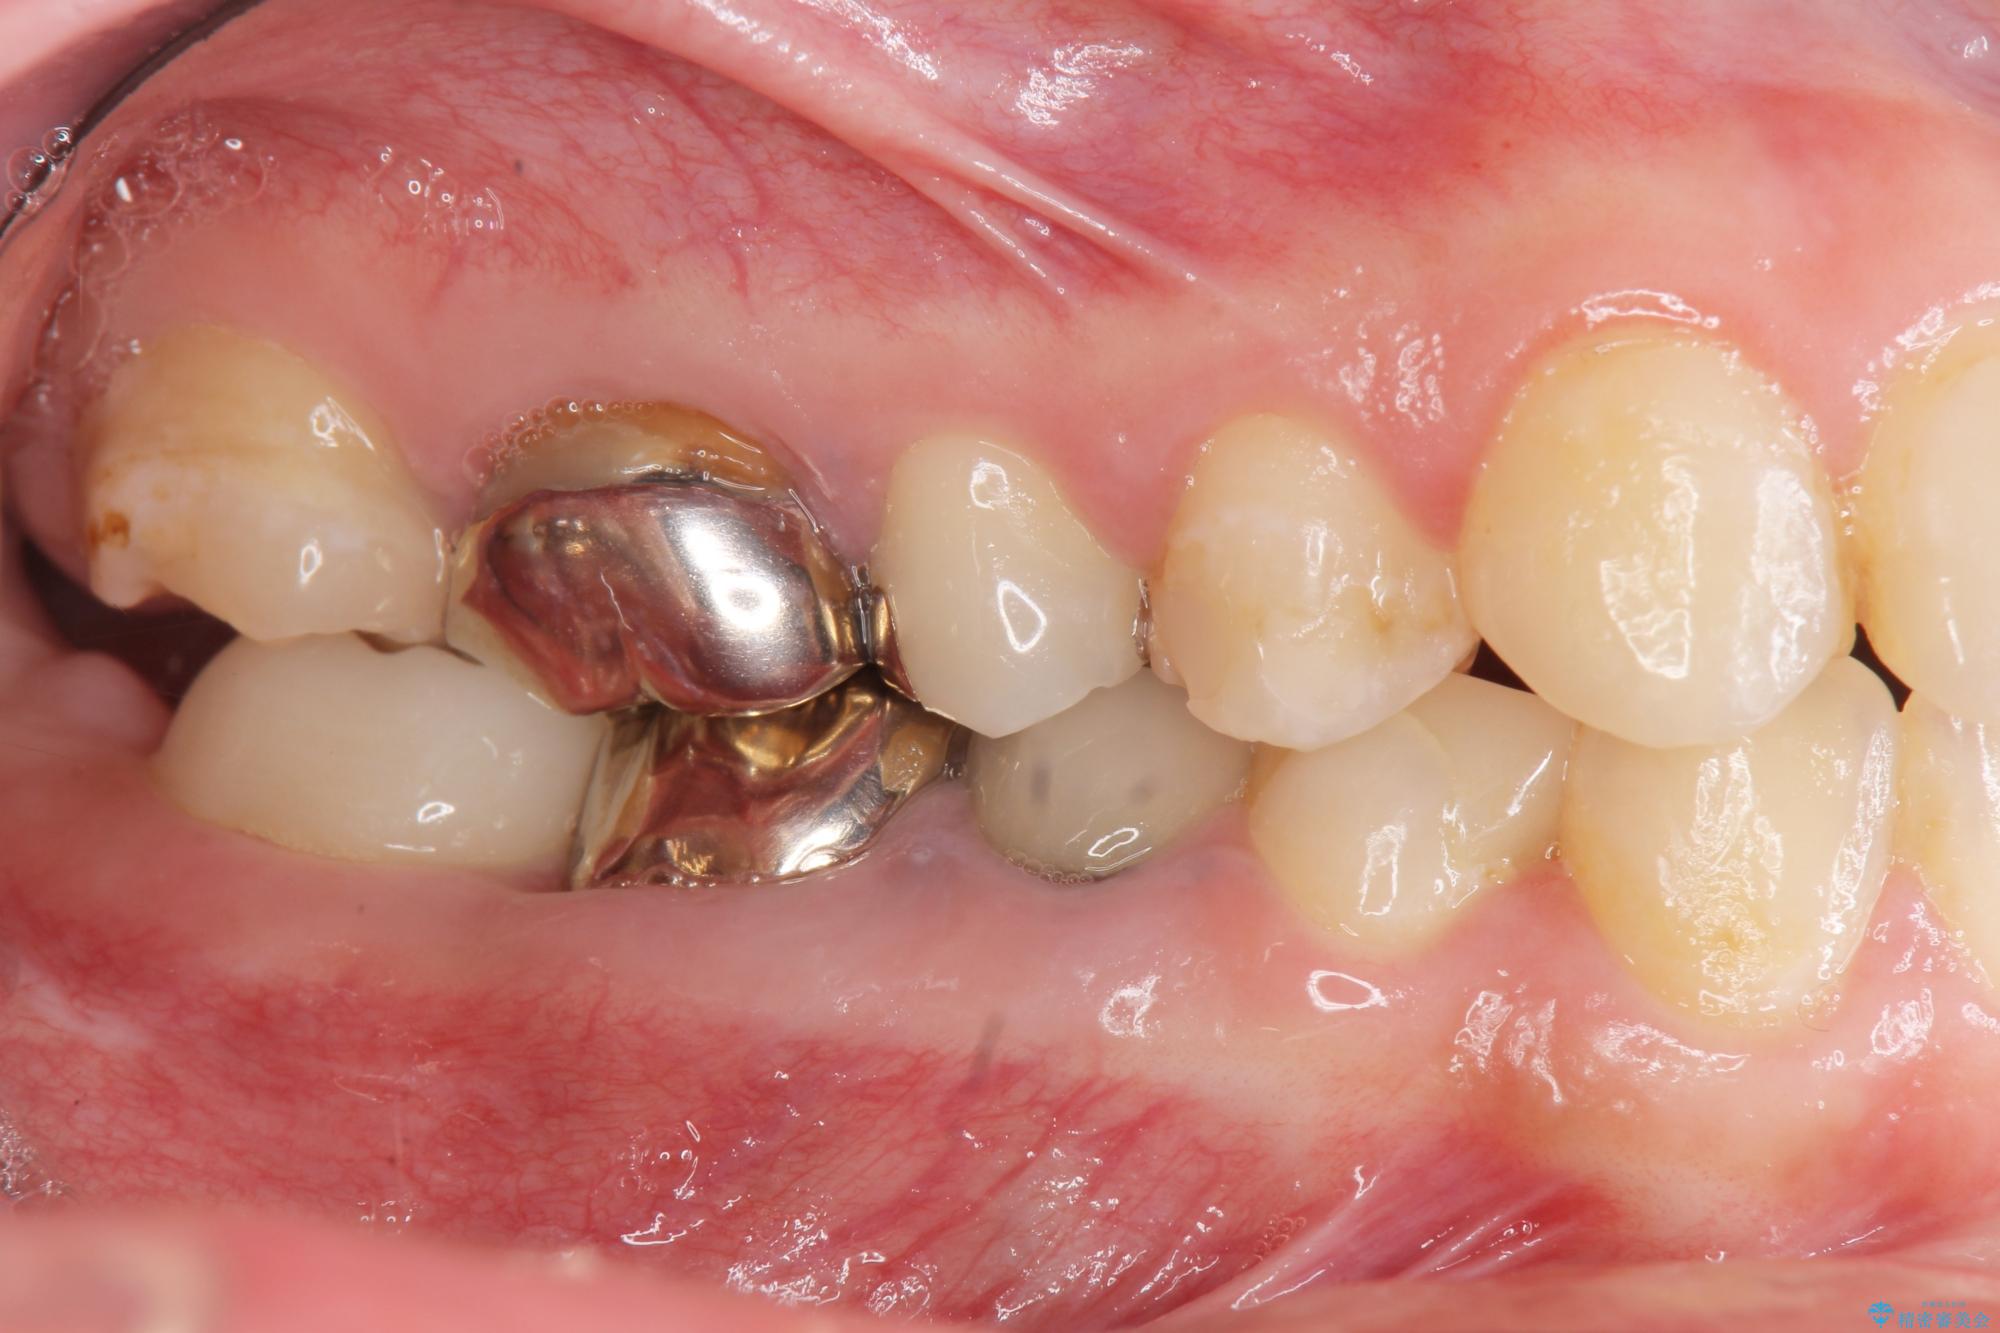

X線写真検査より、クラウンや銀歯の下で歯に大きな虫歯が発生し、抜歯を余儀なくされる状況でした。

治療前